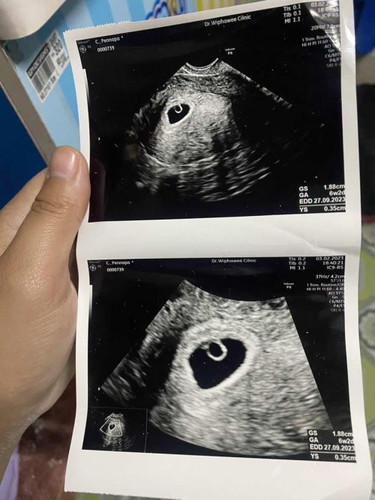

6w3d พบถุงการตั้งครรภ์ ไม่พบตัวอ่อน

ท้องแรก มีภาวะแทงคุกคาม จะมีโอกาสได้เห็นตัวน้อยมั้ยค่ะ ตอนนี้มีเลือดออกนิดๆแบบเปลื้อนๆ กังวลมากเลยค่ะ ทำไงถึงจะผ่านไปได้ด้วยดีค่ะ